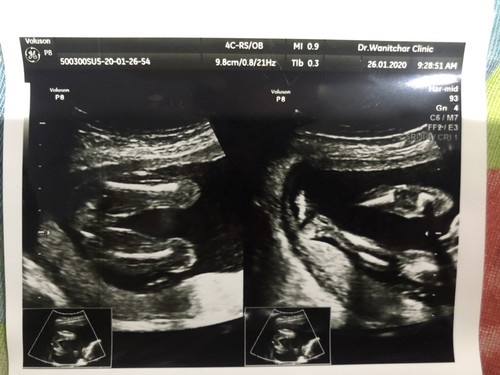

ตอนซาวด์ตอนนั้นอายุครรภ์ได้ 20 w ยังข้องใจอยู่หมอบอกน้องผู้หญิง แต่ภาพแรกเหมือนน้องมีจู้เลยคะ แม่ๆว่าจะได้ชายหรือหญิงจ๊ะ ปัจจุบันอายุครรภ์ 33w+2 แล้วจ้า???